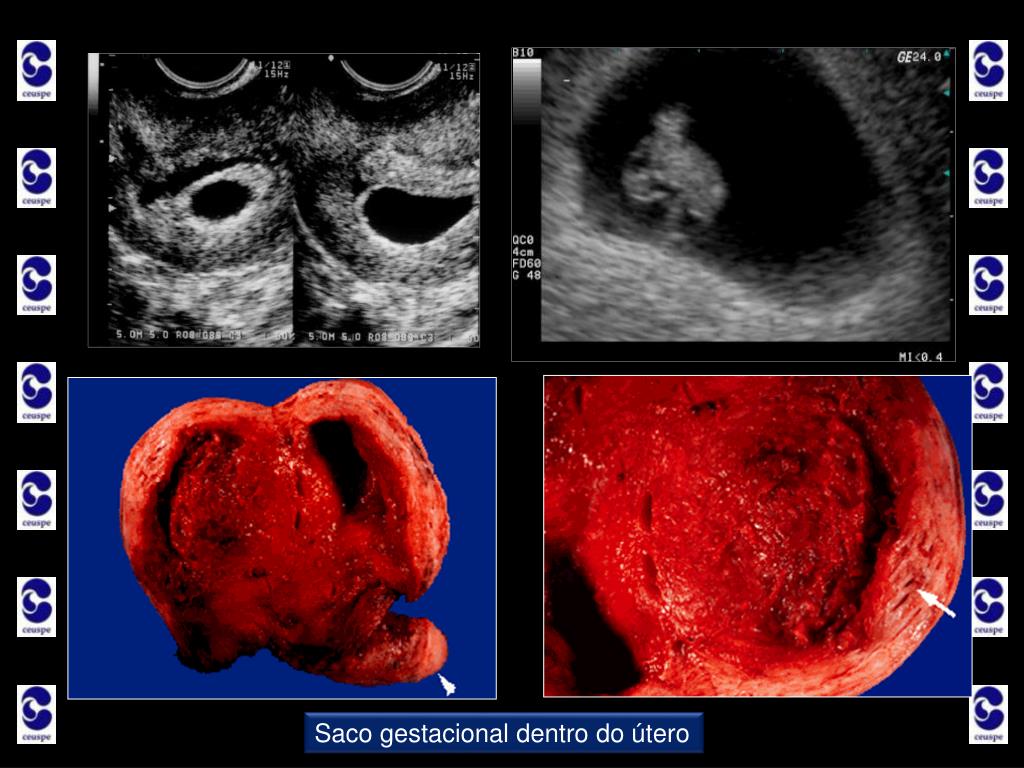

3. Ultrassonografia nos primeiros três meses Sua importância • Primeiro Trimestre • Idade Gestacional • contada a partir do primeiro dia da última menstruação; • a gestante deve estar atenta para fornecer com segurança o primeiro dia da última menstruação; • o exame de ultrassom nos primeiros 3 meses dá a data provável do parto de forma mais precisa, com erro médio de 4 dias para mais ou para menos; • quando a menstruação não vem, a gestante já está com 4 semanas na contagem do médico obstetra;

4. Ultrassonografia nos primeiros três meses Sua importância • Primeiro Trimestre • Idade Gestacional • um exame de sangue chamado beta-hCG confirma a gravidez; • a gestação começa a ser vista dentro do útero da mãe com um atraso aproximado de de 3 dias na menstruação, quando ela já tem uma idade de gravidez de 4 semanas e 3 dias na contagem do obstetra; • o exame de ultrassom no início é importante para termos a certeza de que a gravidez está dentro do útero, pois existem casos em que o saco gestacional se implanta fora do útero. Por exemplo, em uma das trompas da mulher;

11. Saco gestacional dentro do útero